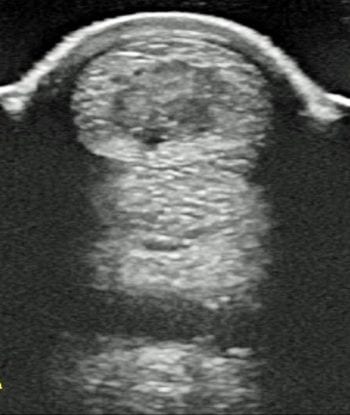

Intralesional injection of PRP or bone marrow-derived MSCs – with or without laser therapy – represent the best treatment options available; however, with re-injury rates remaining high, a need exists to better understand the cellular mechanisms of tendon injury, which could lead to a more effective treatment in the future.